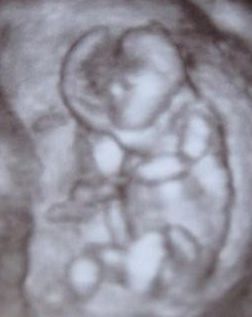

A kép a kislánykáról:) Hát nem tudom, hogy mennyire fog látszani.

Ilyesztőnek tűnik a fejecskéje egy nem hozzá értőnek - köztük nekem is - mert az nem lyuk a fején, hanem a kutacs..:)

Ezen a képen a terminus szerint 12 hetes 2 napos volt. Ugyanakkor a méretei alapján 13 hetes 2 napos volt. Tehát 1 héttel nagyobbnak mutatta magát.

Szóval ez a 4D -s kép. Egyébként nagyon szépen látszottak az újjacskái a kezén és a lábán is..hihetetlen úgy mozgatta a lábán az újjait..nem tudnám utánozni:)

Hanem az ultrahang során több pozícióból megnézték..többek között a gerincét, az orrát, a lábait, a fenekét..no és ott sima volt a felület..nem volt herezacsika és fütyi sem..no valahogy így kell elképzelni.

Ez a kép nem adja vissza azt amit láttunk, nem igazán jó pozicíóból készült a kép.

Kaptunk CD-t is, no az igazán élménydús:) -számunkra-.

A fejétől a fenekéig 7 cm + a kis lábacskái. Hát olyan 10-12 cm lehet teljes egészében, de ezt nem mérik le.

A tarkóredő nekünk 0,9 mm volt Ami jó.

Mert a 3cm felett az már veszélyes.

Azt mondta a doktornő aki vizsgálta, hogy a lényeg még az, hogy ilyenkor már kell, hogy az orrcsont is kiálljon, mert az a normális..hát van is neki pisze orrocskája.

A véleményem, hogy igazán a 4D uh az a 25-héttől mutat igazán szép képet a babáról, ilyenkor csak nekünk gyönyörű a látvány:)